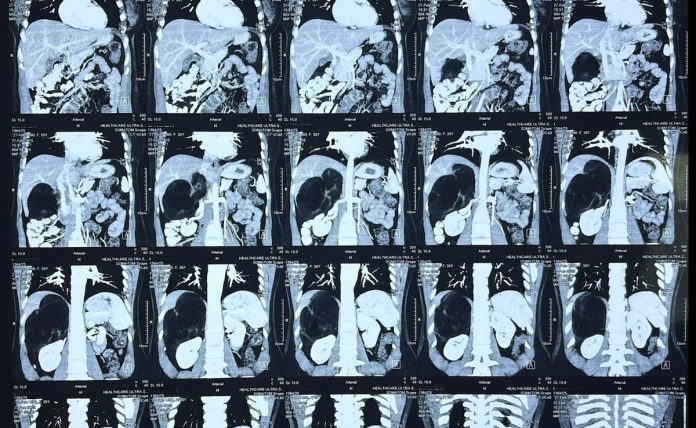

सफदरजुंग हॉस्पिटलचे वैद्यकीय अधीक्षक डॉ. संदीप बन्सल यांनी माहिती दिली की १.2.२ x १.5. Cm सेमी मोजण्याचे ren ड्रेनल ट्यूमर, जगातील जगातील सर्वात मोठे ren ड्रेनल ट्यूमर आहे जे रोबोटिकल कमीतकमी आक्रमक फॅशनचे स्मरण केले गेले आहे.

ही प्रक्रिया धोक्यांसह माइंड कावा, यकृत आणि योग्य मूत्रपिंडासह घसरली होती.

आसपासच्या रचनांचे नुकसान न करता ट्यूमर त्याच्या प्रवेशामध्ये काढण्याची आवश्यकता आहे. डॉ. वासुदेव यांनी असे म्हटले आहे की अशा शस्त्रक्रिया करण्याची तंतोतंत विच्छेदन ही एक महत्त्वाची गुरुकिल्ली आहे आणि दा विंची रोबोटची थ्रीडी व्हिजन, त्याच्या डेक्सट्रस रोबोटिक शस्त्रासह, एखाद्याला लेप्रोस्कोपीसह सामान्यत: शक्य असलेल्या गोष्टींपेक्षा महानतेसह कंपनी करण्यास परवानगी देते. या प्रकरणात, शस्त्रक्रिया तीन तासांपर्यंत चालली आणि कोणत्याही गुंतागुंत न करता ट्यूमर पूर्णपणे काढून टाकला जाऊ शकतो. ऑपरेटिव्हनंतरची पुनर्प्राप्ती असंतोष होती आणि तीन दिवसांत रुग्णाला सोडण्यात आले.